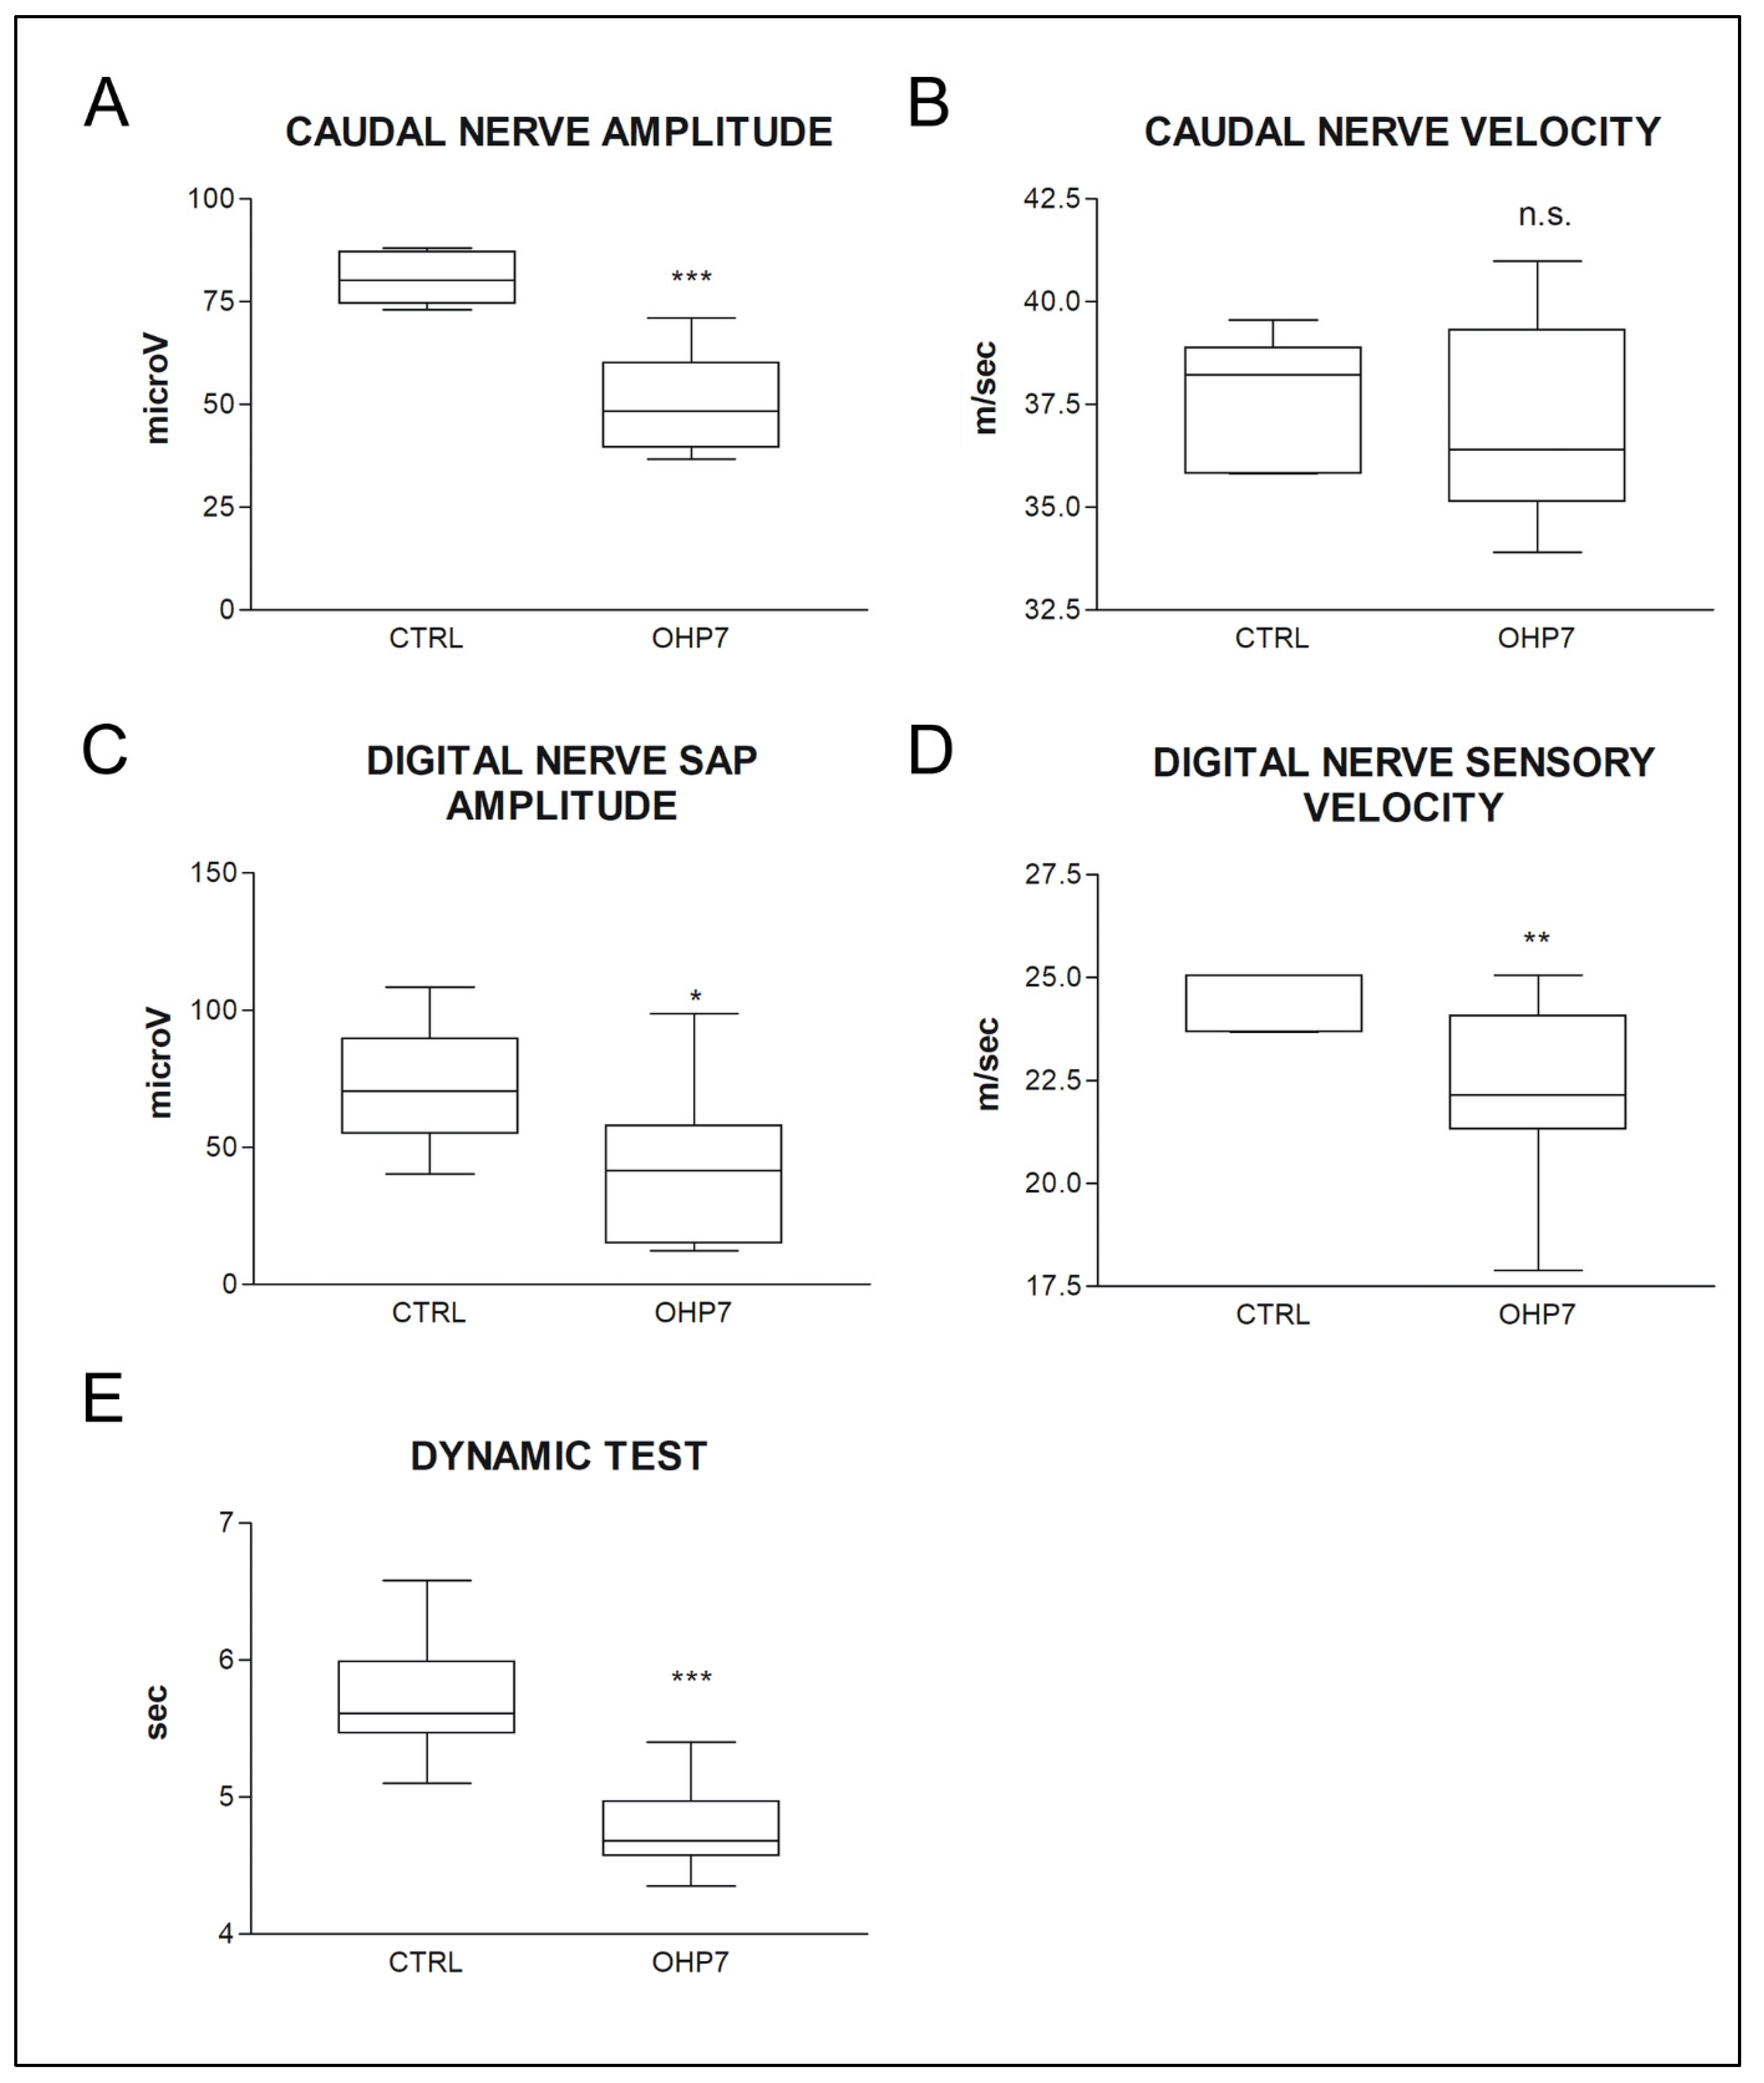

2.2.2. NCS and Behavioral Tests at the End of Treatment